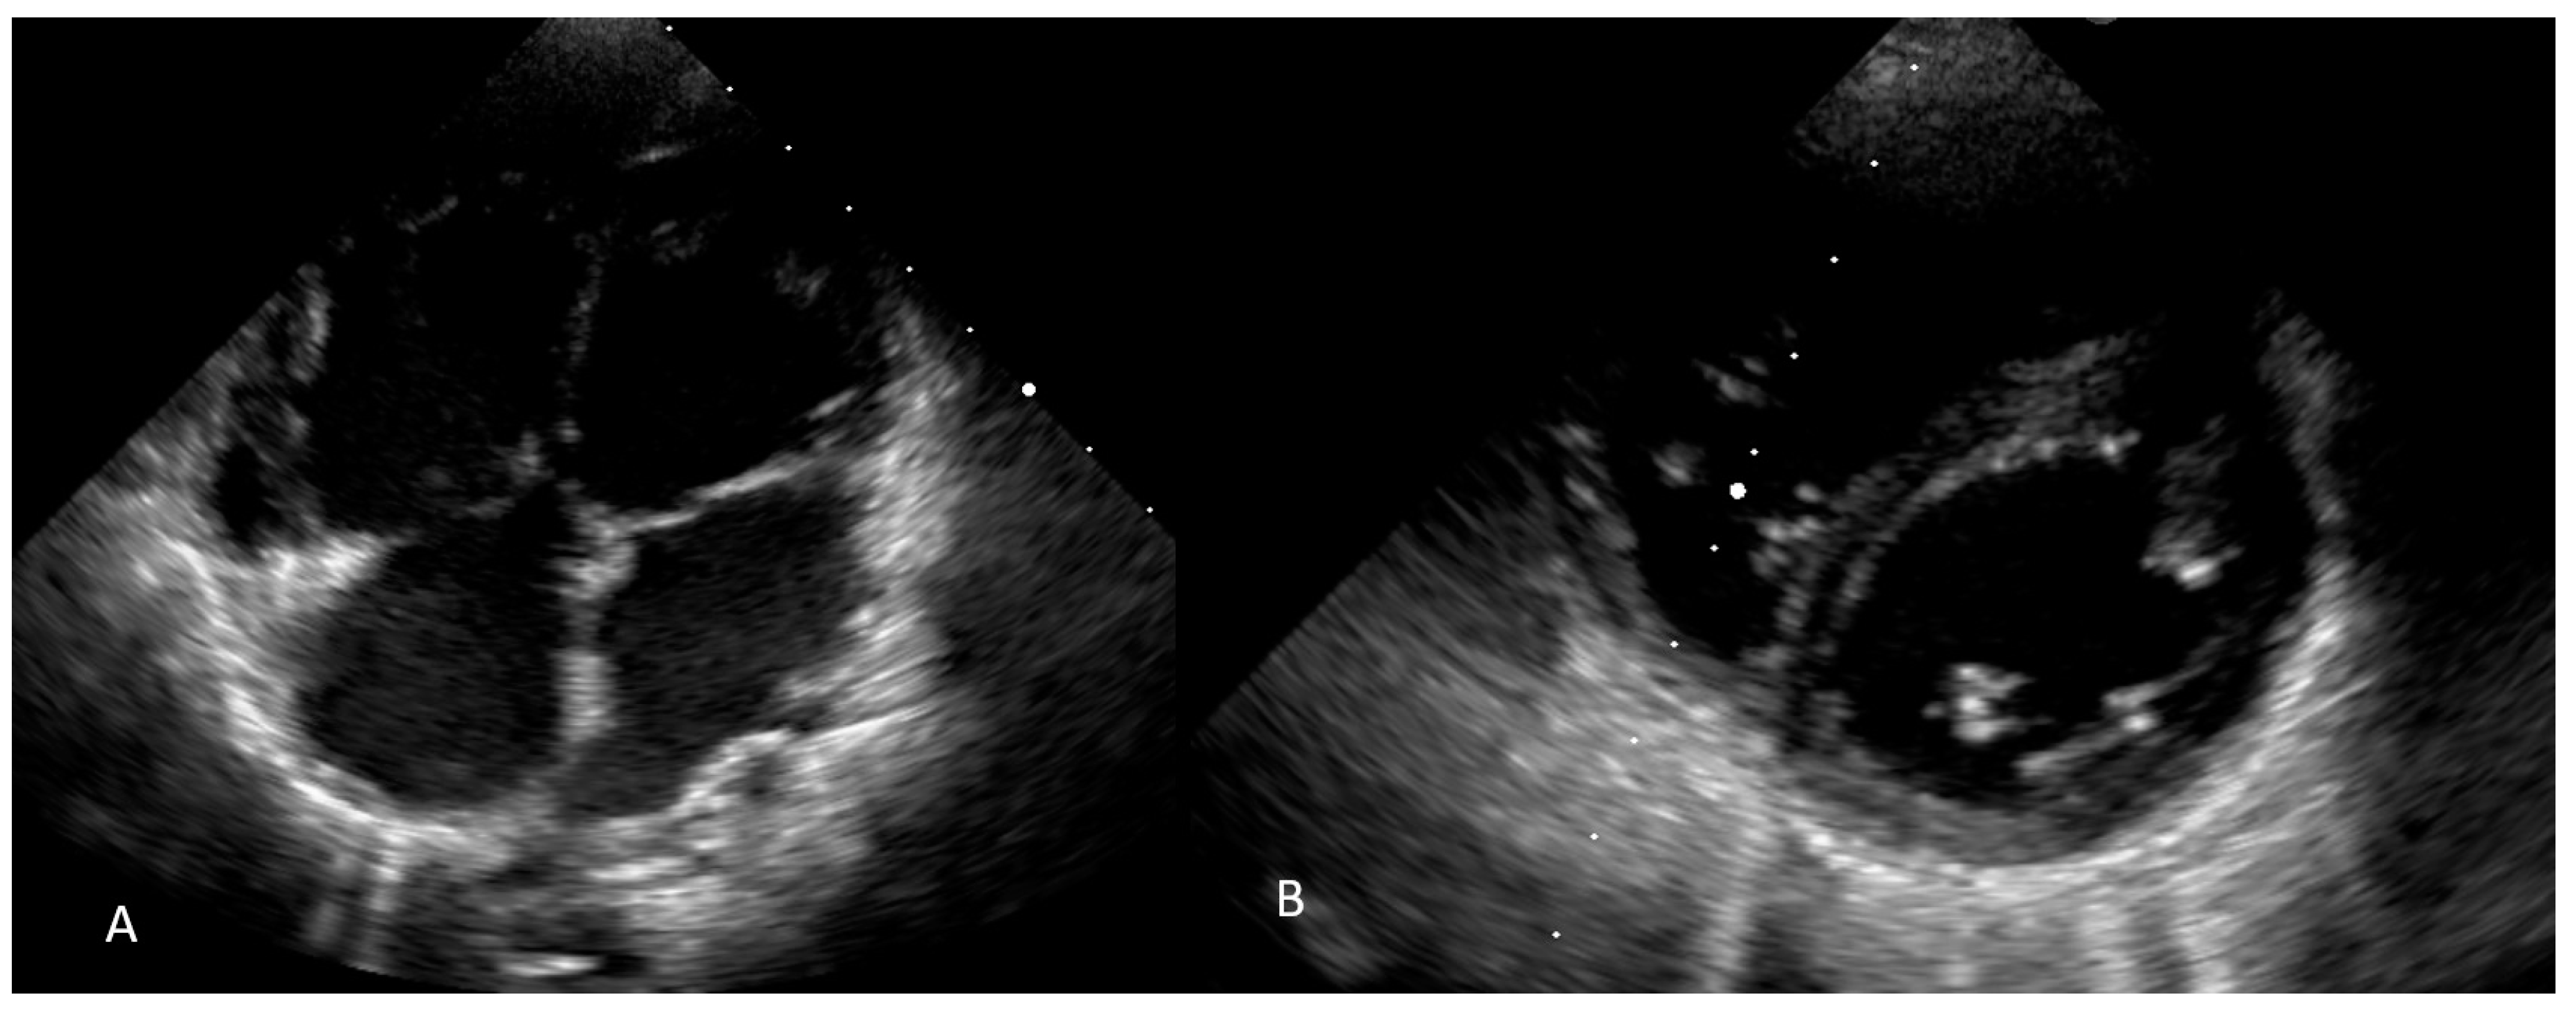

2.2. Diagnostic Assessment